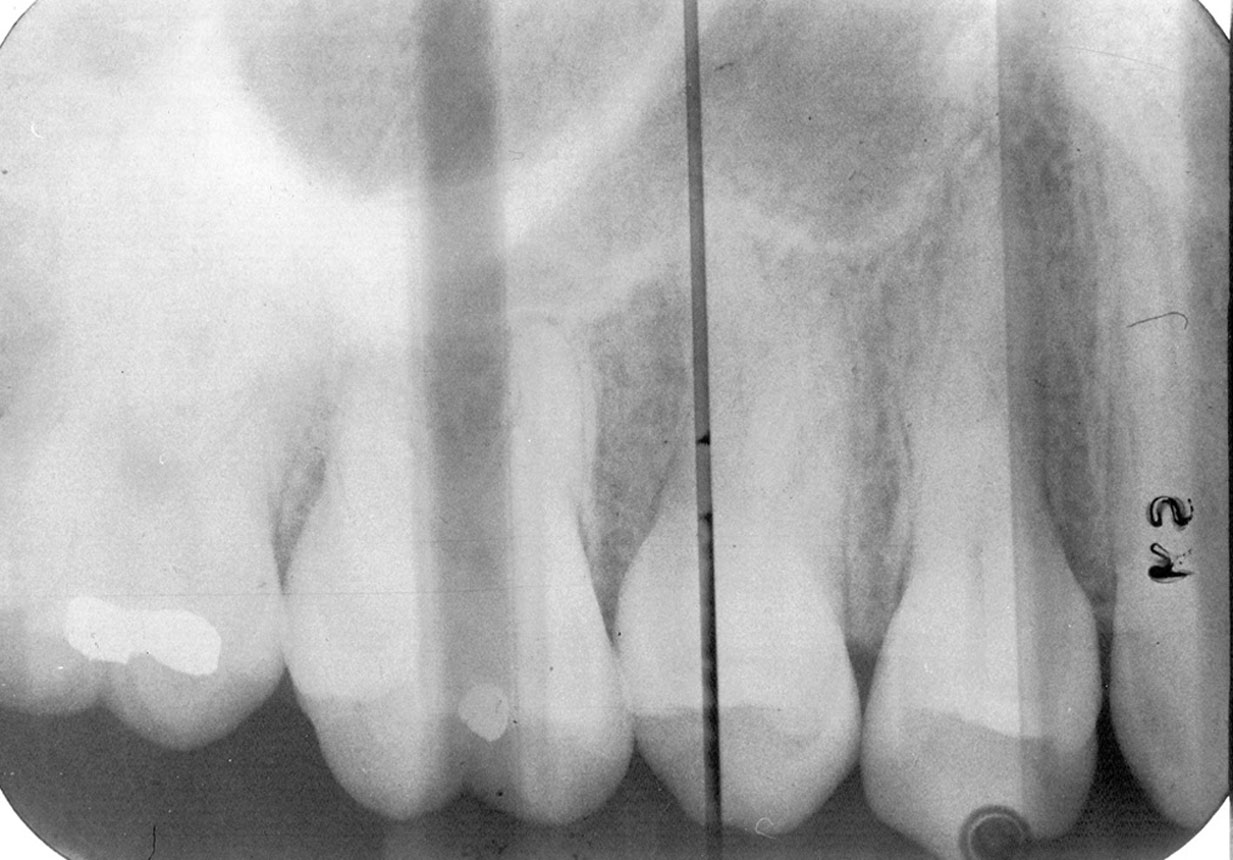

Proximal (Horizontal) Overlap

Description: To open the interproximal contacts between adjacent teeth, the horizontal angulation of the x-ray beam needs to be parallel to the teeth and film being exposed. In particular, the central ray of the x-ray beam must be at a 90º angle to the interproximal areas desired in the film. If it is not, the surfaces will overlap, causing image superimposition of adjacent teeth, which appear as teardrop shaped, light regions between the teeth on the radiograph (Figure 6).

Differential Diagnosis: The light, droplet-shaped areas between the teeth indicate proximal overlap. The central ray or beam was not parallel with the interproximal surfaces. If the overlaps are larger in the posterior half of the film, the horizontal angulation was angulated too much from the mesial toward the distal. The reverse is true for a film in which the overlaps are larger in the anterior half of the film.

Consequences: Important information about incipient interproximal caries can be obscured. The darker lines that form at the zone of changing density in overlapping areas could be misinterpreted as interproximal caries.

Remedy: The operator should review technical procedures regarding horizontal angulation and repeat the film. The operator should be directing the central beam into the interproximal spaces of the teeth needing to be radiographed.

Figure 6. Proximal overlap.

Figure 6